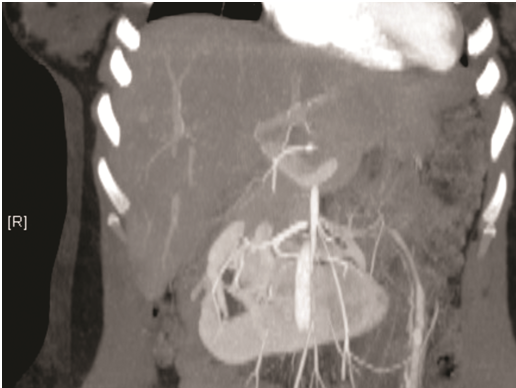

A 28years female with past history of laparoscopic cholecystectomy presented as an emergency with first episode of gross hematuria and clot retention. She was catheterized and bladder irrigation was performed. Serum creatinine was normal. Computerized tomography revealed horseshoe kidney. Cystoscopy and retrograde pyelography was unremarkable. As hematuria persisted, CT angiogram was done which showed hoarse-shoe kidney (Figure 1).

Figure 1 Hoarse-shoe kidney.